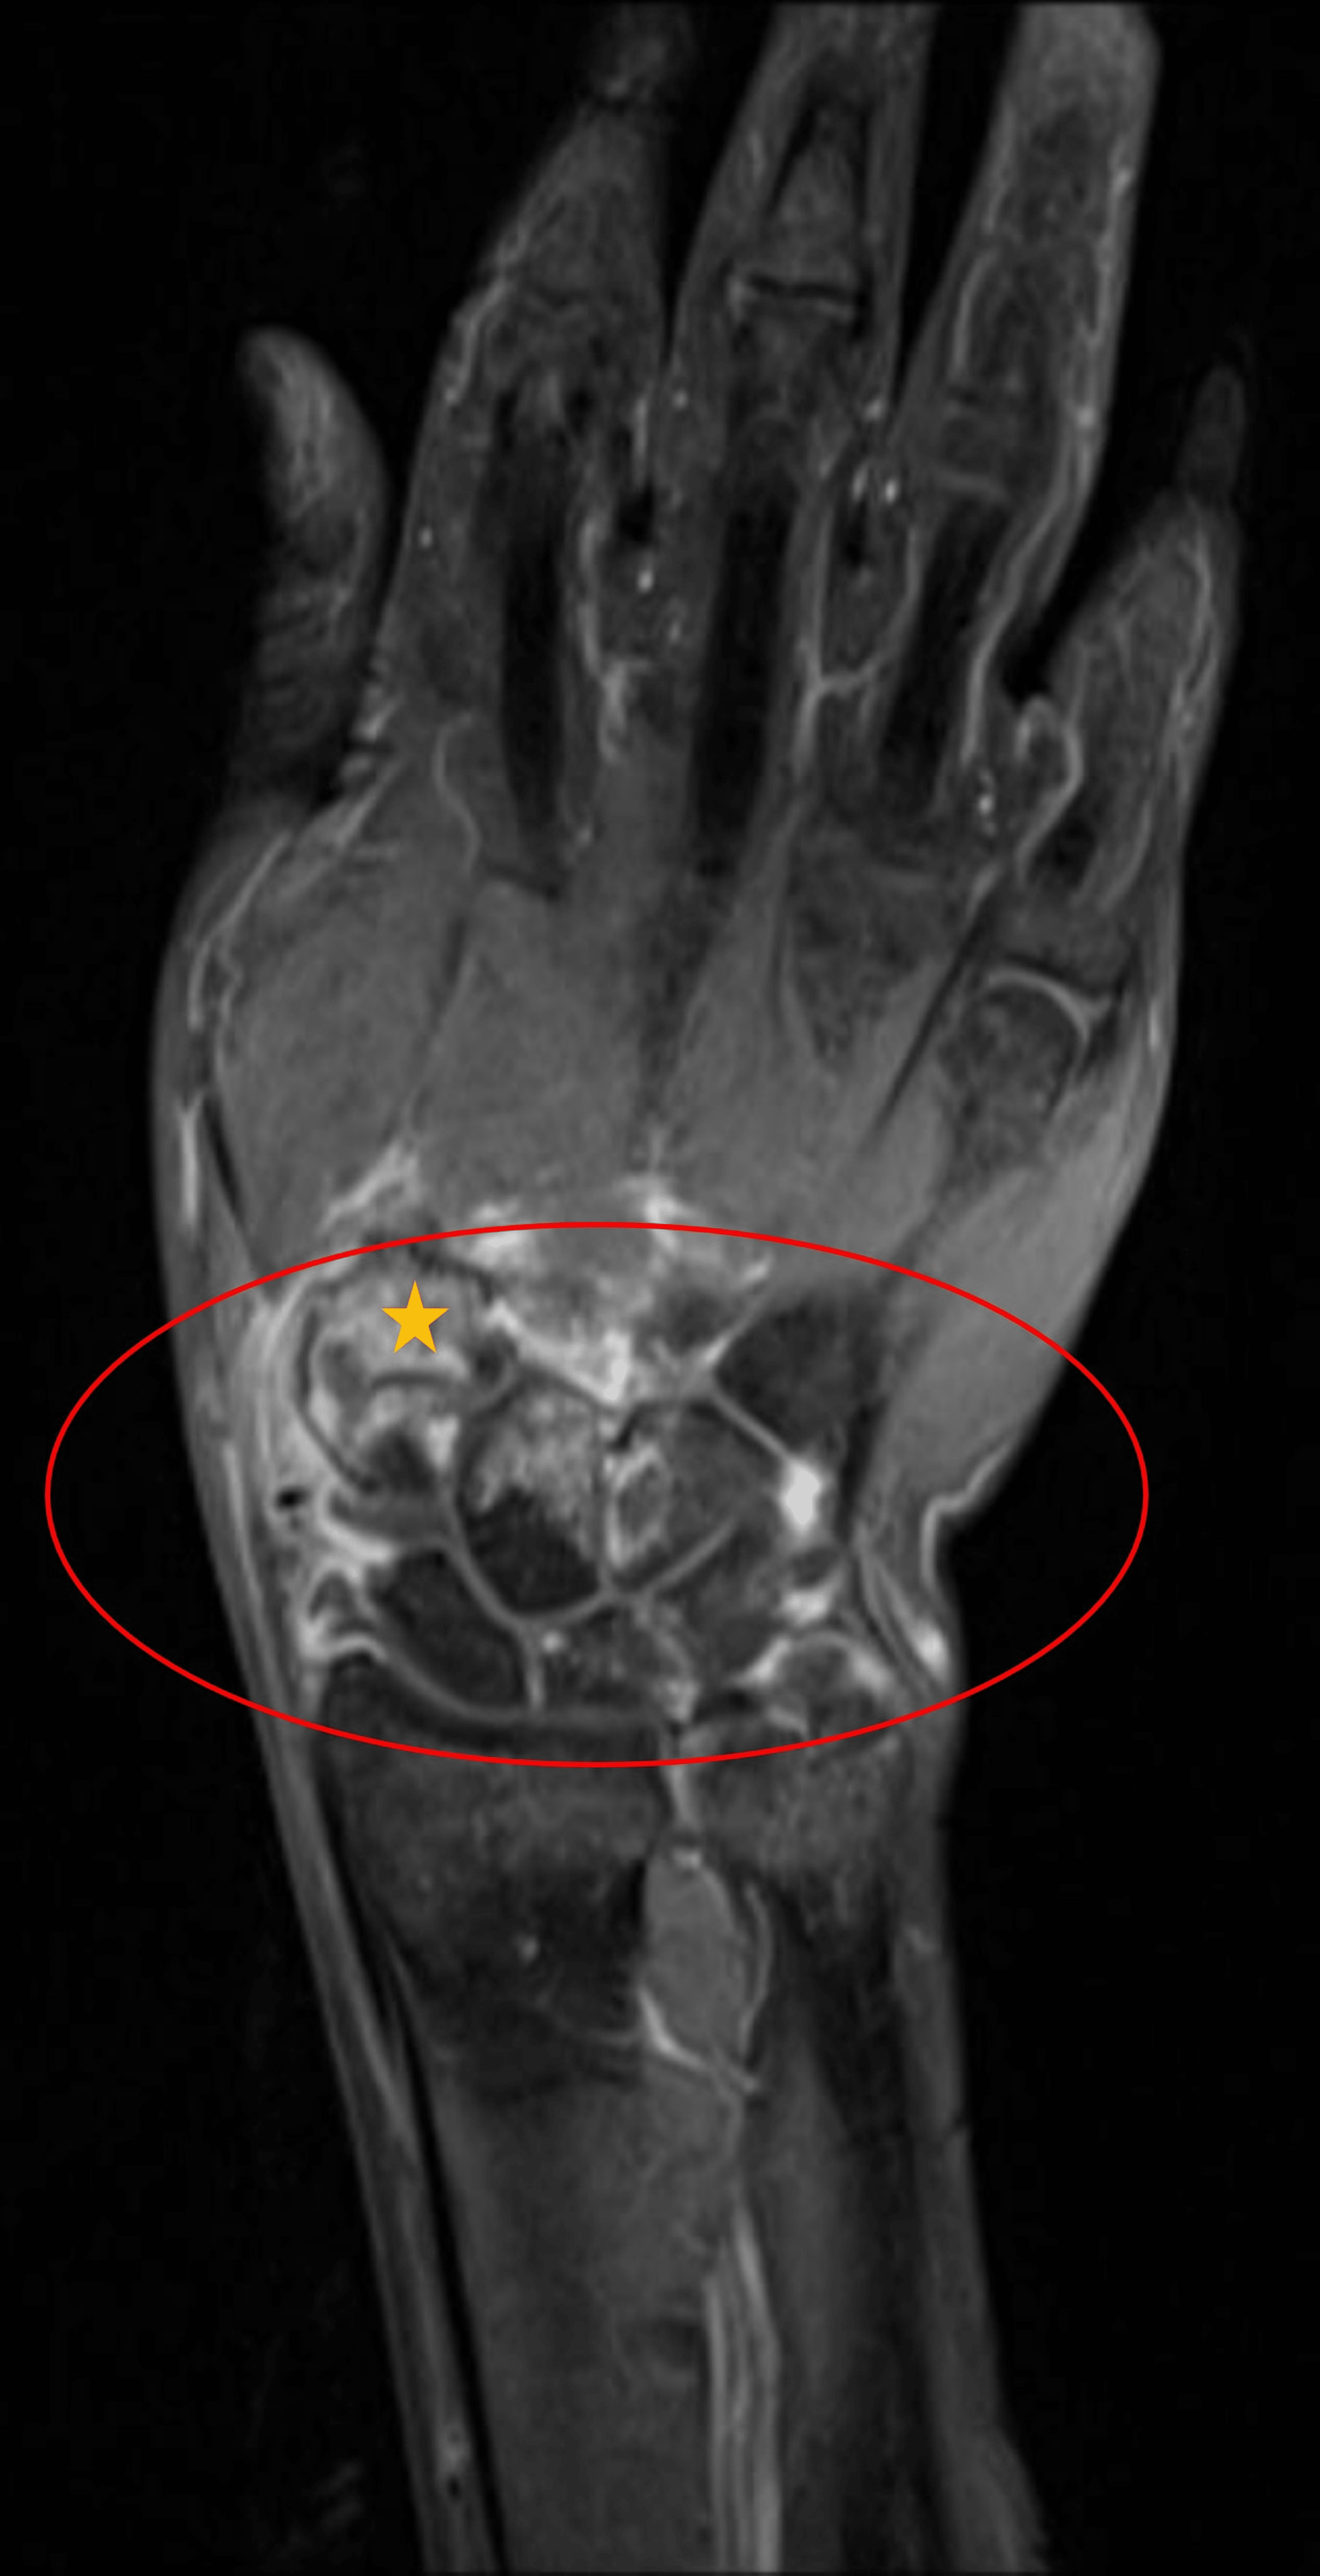

From www.researchgate.net

Coronal T2weighted scan of the left wrist showing joint effusion with Joint Effusion Wrist Treatment Learn how to diagnose and treat it, and how long it. It can result from injury, infection, arthritis, or autoimmune disease. learn about the common causes of wrist pain, such as fractures, sprains, strains and carpal tunnel. you can help treat swollen joints by applying ice, resting painful joints from aggravating movements, and talking to your healthcare provider. Joint Effusion Wrist Treatment.